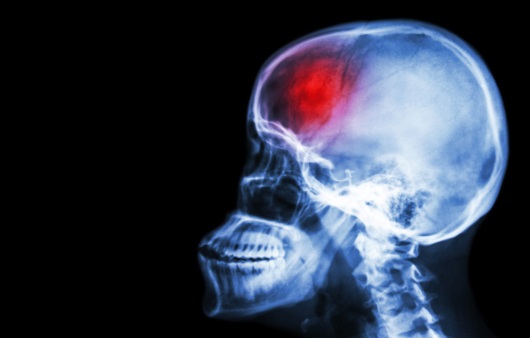

안녕하세요 오늘은 뇌졸중 징조 원인 과 예방법에 대하여 알아보려고 하더라고요. 더운 날씨가 지나고 점차 추워지면 보통과 다르게 다르게 뇌졸중의 위험이 증대하는데요. 우리에게 흔하게 있는 두통 역시 뇌졸중의 조짐일수도 있어요.

뇌졸중은 뇌 일부에 혈액을 조달하는 혈관이 막히거나 파열돼 뇌 손상을 발생시키는 질환으로 의식장애, 부분마비, 언어장애 등 각가지 신경학적 결함을 대동한다고 하고요. 뇌졸중은 뇌혈관 질환과 같은 말이며 우리나라에서는 중풍이라고 곧잘 말하고 있죠.

뇌졸중은 주로 동맥경화증으로 뇌조직으로의 혈액 공급이 차단돼 뇌 손상을 촉발하고 흡연, 과음, 운동 부족, 비만 등이 원인이고요.뇌졸중은 보통과 다르게 추운 날씨에 생성되기 쉽다고 하는데요. 추울 때는 혈관이 수축하고, 더울 때는 팽창하기에 추운 곳에서 급격히 실내로 들어오면 혈관이 급작스레 확대되기 때문이예요.